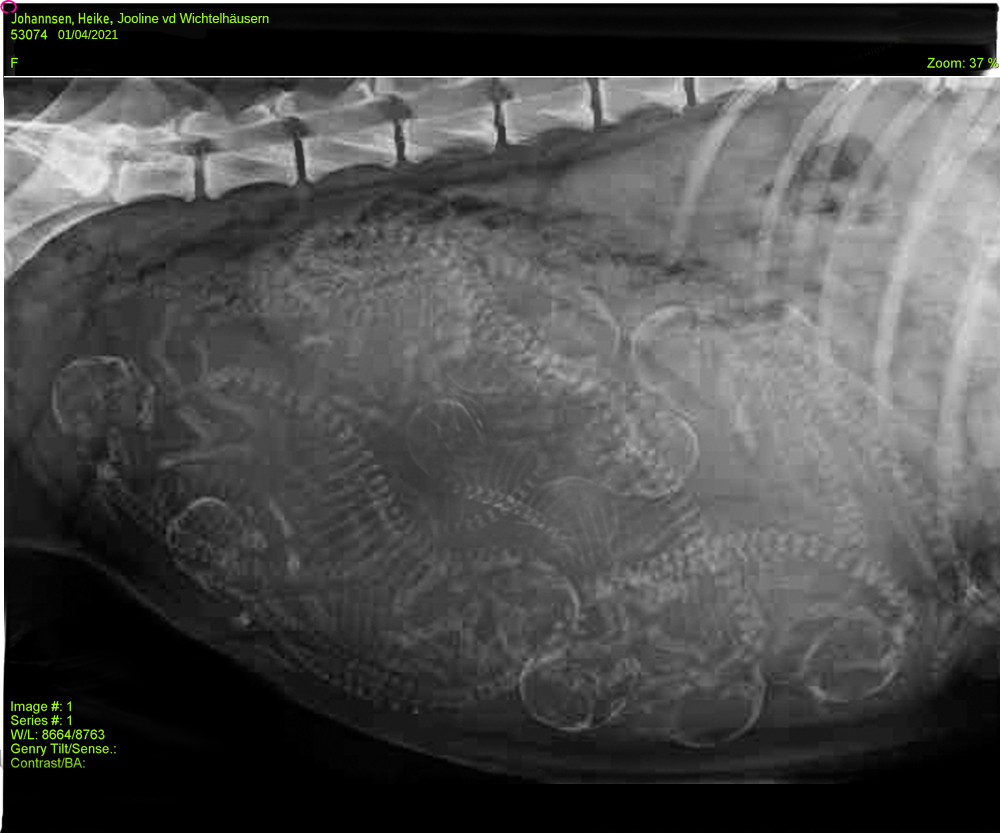

Ich glaube, sooooo einen dicken Bauch

habe ich noch nie gesehen. Weil es mir schon ein bisschen unheimlich erschien, sind wir nochmal in die Klinik gefahren um alles durchzuchecken und wir haben ein Röntgenbild gemacht.

Fazit: ALLES BESTENS !!!

Wir konnten 11 Welpen einwandfrei erkennen und wie es aussieht, sind die auch noch ordentlich groß. Das wird sicherlich kein Zuckerschlecken. Die Aufregung steigt. BALD haben wir es geschafft - noch max. 9 Tage.